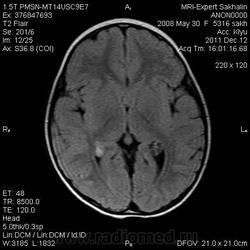

Девочка 3 года.В анамнезе -родовая травма-внутрижелудочковые кровоизлияния 1-2 ст.Задержка психического развития.Со слов мамы, "бывают истерики, хватается ручками за голову, особенно затылочную часть".Как интерпретировать изменения в желудочках, в задних рогах?Ликворную кисту ЗЧЯ отметила.

А вот гипоинтенсивное по Т2 в заднем роге левого бокового желудочка?В других последовательностях нет.

справа киста сосудистого сплетния -она же ксанутрогранулема,пртекаетбессимптомно.в эру доКТ и МРТ диагнстировались только на аутопсии,влевомсплетении -фокус пониженного МРС -возможно обезыствление или гемосидерин  ( ведь было кровоизлияние?)